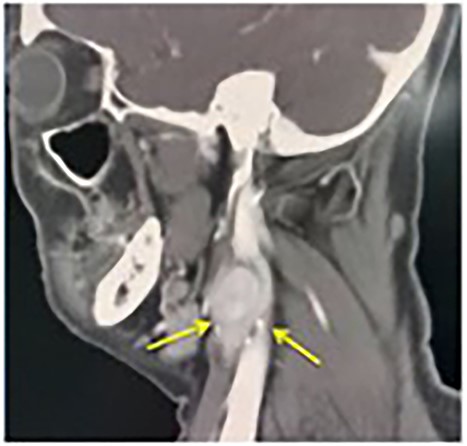

A contrast-enhanced computerized tomography (CECT) of the neck showed bilateral enhancing mass at the both carotid bulbs (Fig. 1), sandwiched between the external carotid artery (ECA) and the internal carotid artery (ICA) giving a positive Lyre sign. The CECT showed the left and the right mass measuring 3 × 2.5 cm and 2 × 1.2 cm, respectively (Fig. 2). No signs of thrombosis were seen. A two-staged excision was decided by the vascular surgeons and the surgical approach is described as the following.